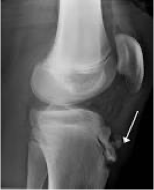

osgood schlatters

what condition?